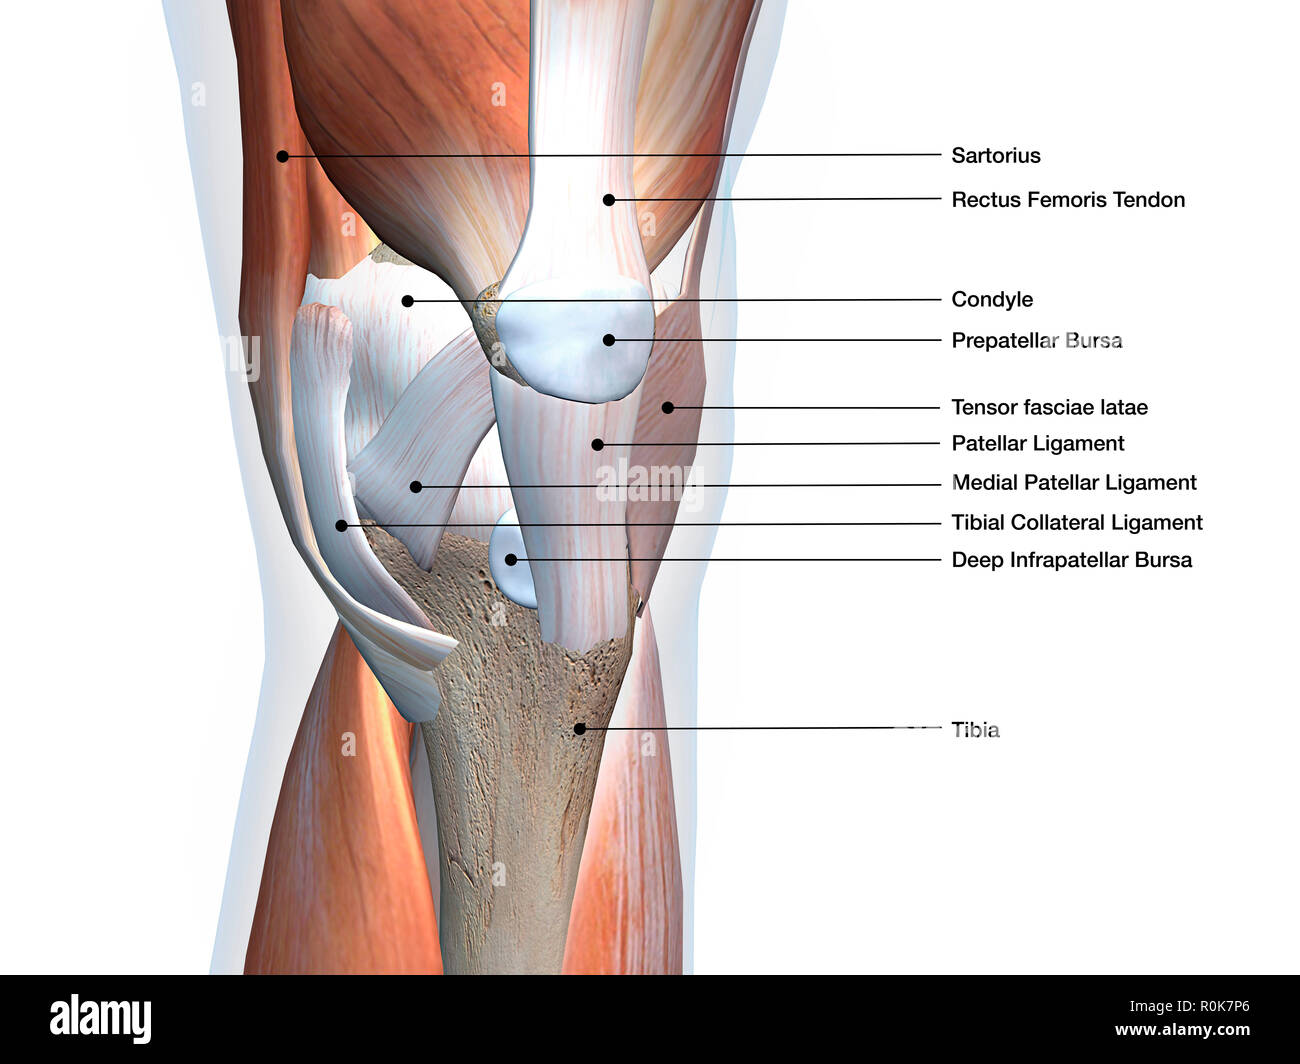

Knee joint showing muscles and ligaments with labels. Stock Photohttps://www.alamy.com/image-license-details/?v=1https://www.alamy.com/knee-joint-showing-muscles-and-ligaments-with-labels-image224157982.html

Knee joint showing muscles and ligaments with labels. Stock Photohttps://www.alamy.com/image-license-details/?v=1https://www.alamy.com/knee-joint-showing-muscles-and-ligaments-with-labels-image224157982.htmlRFR0K7P6–Knee joint showing muscles and ligaments with labels.